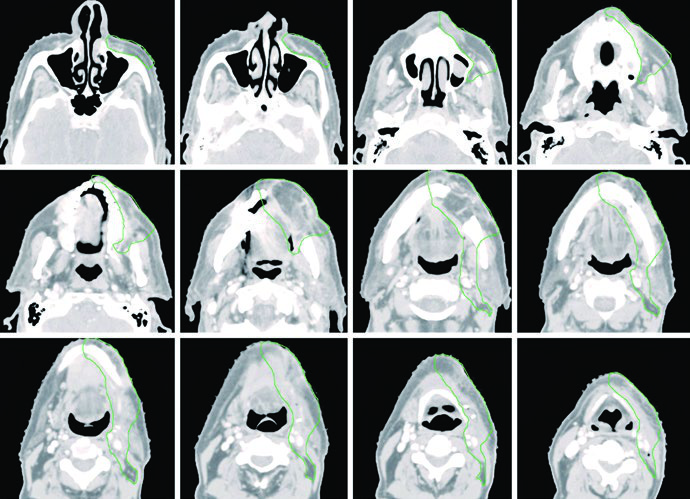

Caso Clínico: Mucosa Yugal T4aN0

La Figura 6.2 muestra un paciente con CEC de mucosa yugal, T4aN0, con invasión cortical ósea mínima, post-resección tumoral con mandibulectomía marginal y vaciamiento cervical izquierdo. Márgenes ampliamente libres. El CTV60 (verde) cubre el lecho operatorio con niveles I a IV ipsilaterales.

El CTV se extiende cranealmente hasta el surco vestíbulo-gingival y fosa infratemporal, caudalmente hasta el surco vestíbulo-gingival y glándula submandibular, anteriormente hasta al menos la comisura labial, y posteriormente hasta el trígono retromolar. Se coloca bolus sobre la piel para garantizar dosis adecuada en el CTV de alto riesgo. Debe considerarse la inclusión de la parótida ipsilateral cuando exista preocupación clínica. Este patrón de extensión del volumen es también relevante para los tumores sinonasales, que comparten proximidad anatómica.